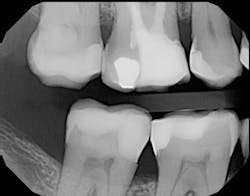

Figure 1 shows a large radiolucency on the mesial and a small radiolucency on the occlusal of tooth 31. Figure 2 shows an initial caries lesion on the distal pit and a leaking occlusal composite. Tooth 31 was sensitive to cold but normal to chewing, bite, and heat. Selective caries removal was used to prevent pulp exposure and preserve the marginal ridge.

Figure 5 is a 36-month follow-up bitewing radiograph demonstrating excellent support of the significantly undermined enamel and deposition of secondary dentin in the mesial pulp horns. Figures 6 and 7 show the occlusal and facial restorations respectively after 18 months. Notice the improvement in shade.